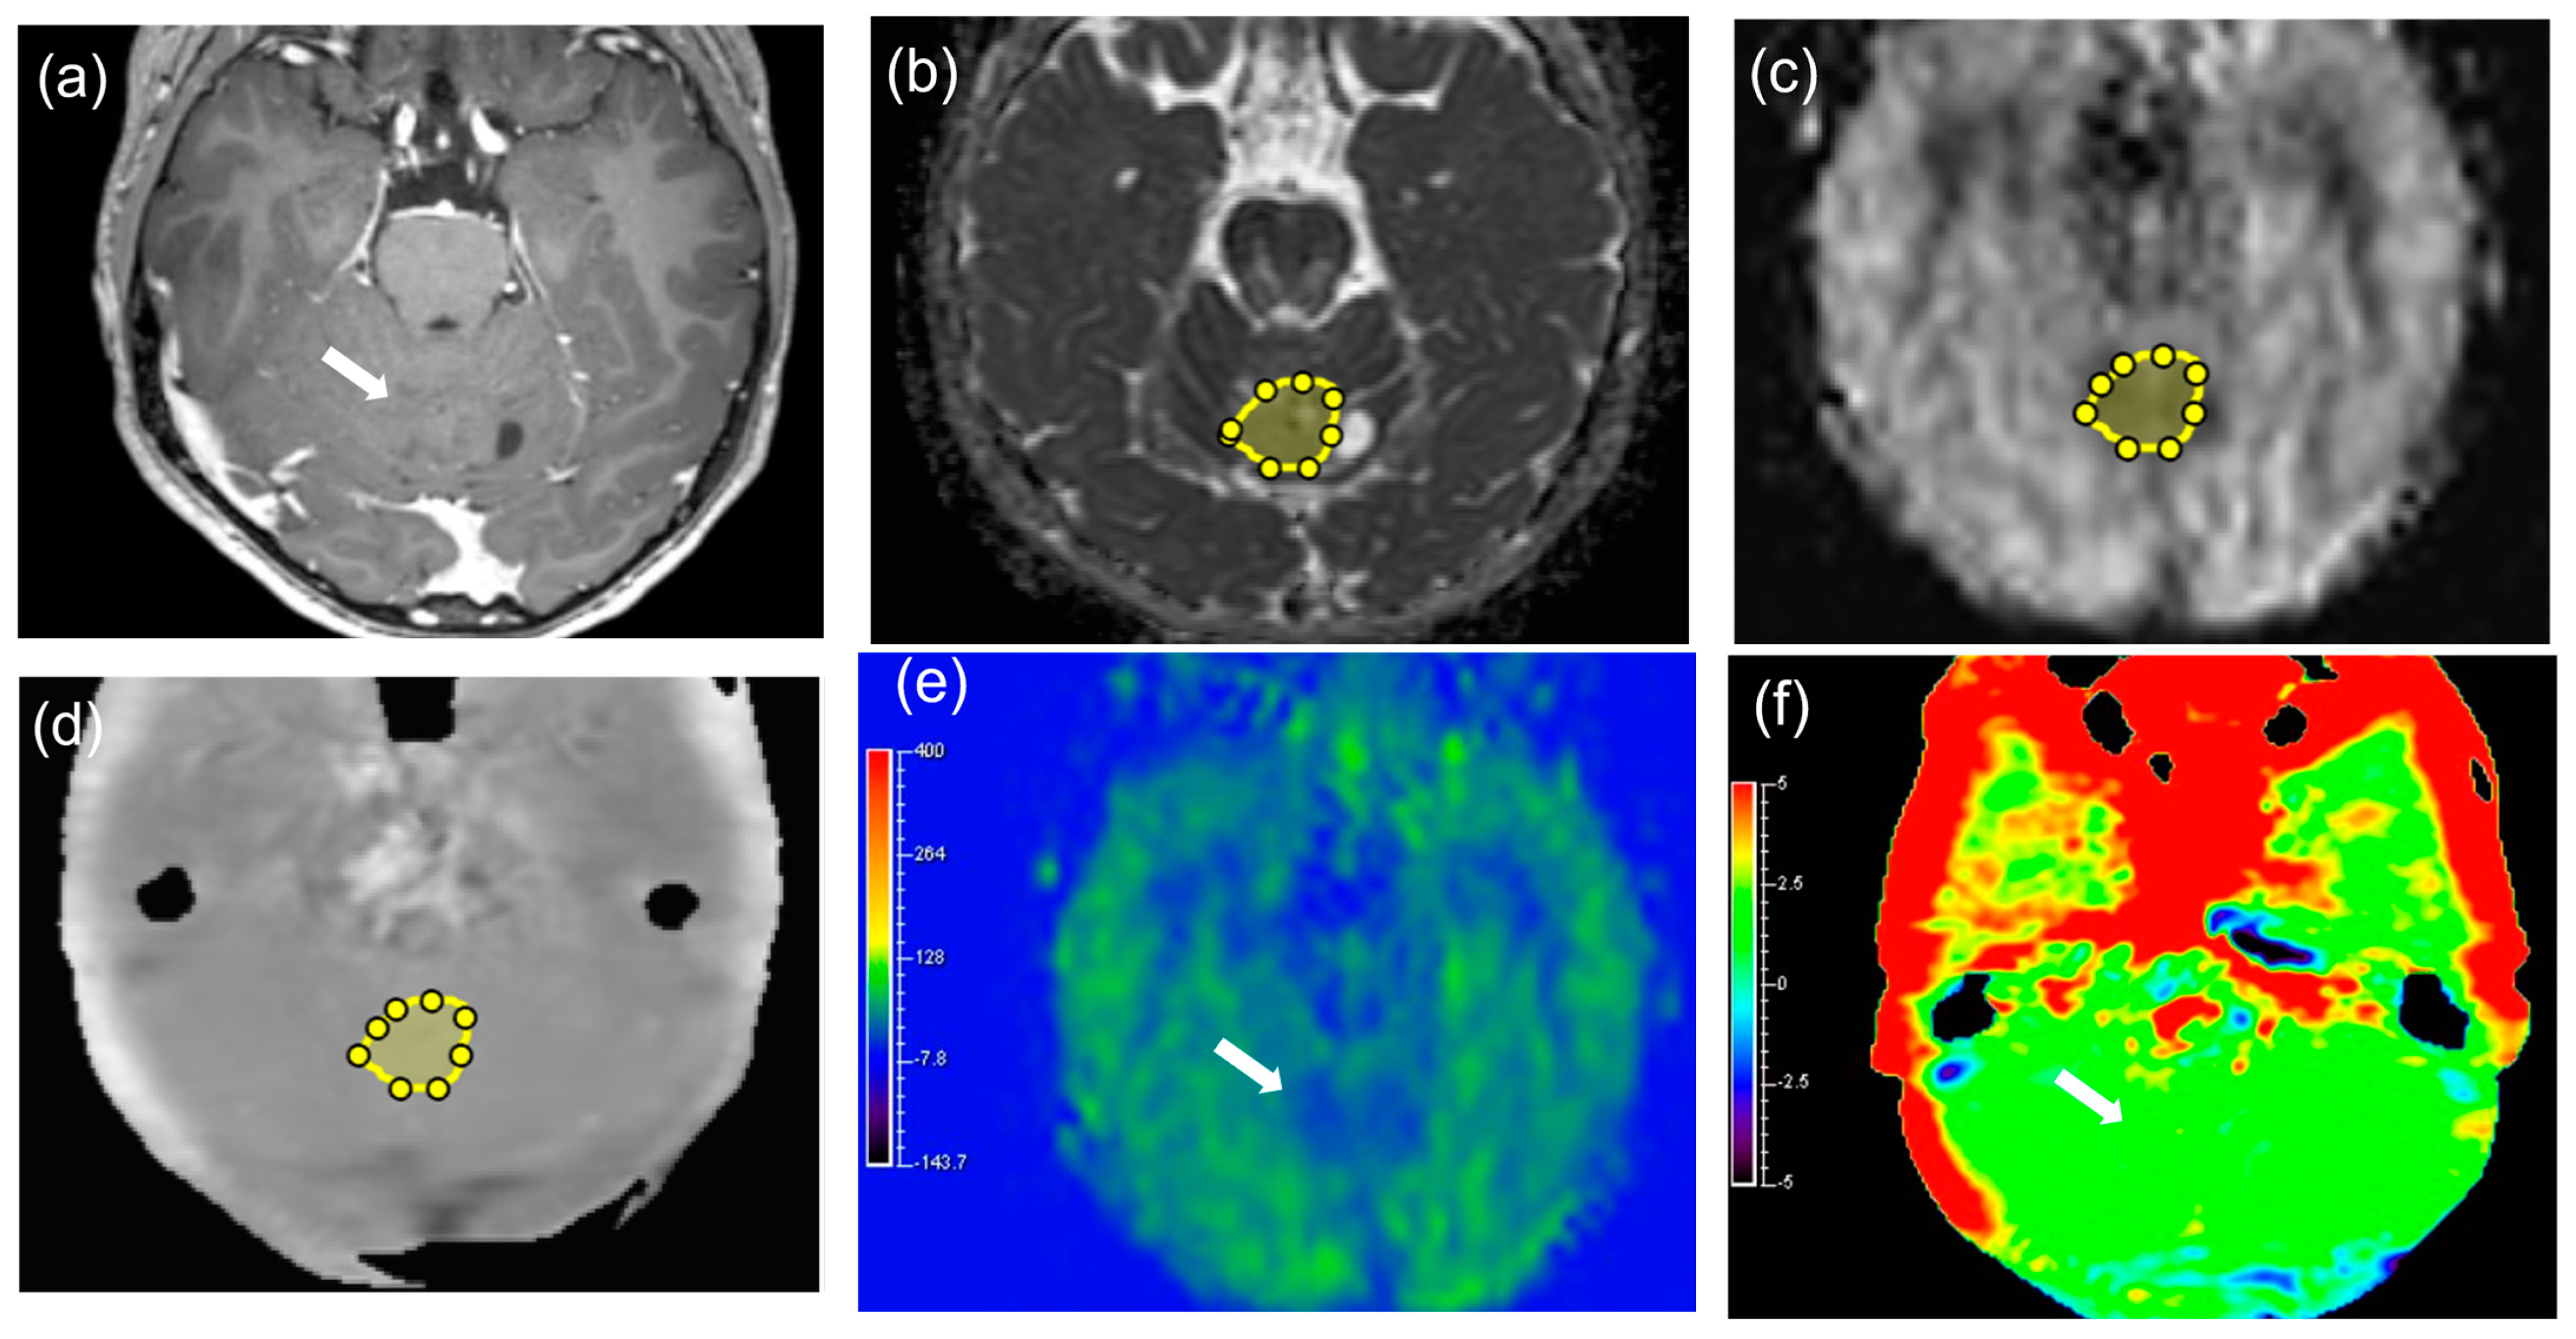

2.3. Image Analysis

3.3. Comparisons of APT, TBF, and ADC Parameters between MTs and BTs

4. Discussion